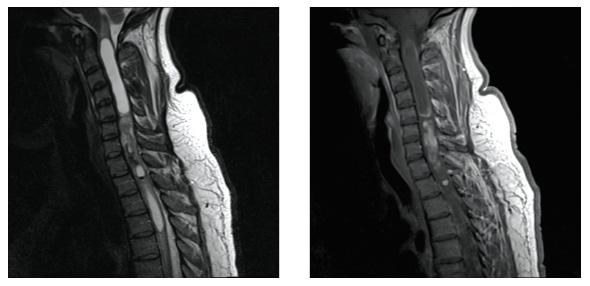

1、髓内肿瘤(Intramedullary Tumors)肿瘤起源于脊髓实质部分(图A),约占椎管内肿瘤的5%-10%,其中胶质瘤常见,如室管膜瘤、星形细胞瘤,起次为血管母细胞瘤表皮样囊肿、皮样囊肿、畸胎瘤以及转移瘤。

2、髓外硬脊膜内肿瘤(Intradural Extramedullary Tumors)肿瘤位于脊髓外硬脊膜内(图B)。此类肿瘤较多,约占椎管内肿瘤的65-70%,大多数为良性肿瘤,如神经鞘瘤、脊膜瘤;少数为恶性肿瘤,如颅内如室管膜瘤或髓母细胞瘤沿着蛛网膜下腔播散转移。

3、硬脊膜外肿瘤(Extradural Tumors)肿瘤位于椎管内硬脊膜外(图C),约占椎管内肿瘤的25%。大多数为恶性肿瘤,如转移瘤、淋巴瘤和多发性骨髓瘤;少数为良性肿瘤如海绵状血管瘤和肉芽肿。